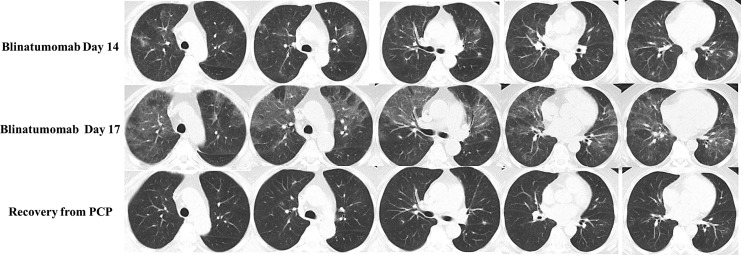

Case presentation: We present a case of PCP in a patient undergoing blinatumomab therapy. A 70-year-old female diagnosed with Philadelphia-like CRLF2 overexpression B-cell precursor ALL received blinatumomab as consolidation therapy after achieving complete remission with prior induction chemotherapy. On the second day of blinatumomab infusion, she developed intermittent low-grade fever, and chest computed tomography (CT) revealed subtle infiltrates and nodules. Despite empiric trimethoprim-sulfamethoxazole (TMP-SMX) prophylaxis, she progressed to significant shortness of breath and type I respiratory failure, with increased lactate dehydrogenase and β-D-glucan assays. Chest CT showed diffuse ground-glass opacities with scattered small nodules. The dry cough prompted next-generation sequencing of peripheral blood, which tested positive for pneumocystis jirovecii without evidence of other pathogens. Consequently, the patient was diagnosed with PCP. The first cycle of blinatumomab had to be discontinued, and therapeutic dosages of TMP-SMX and dexamethasone were administered, resulting in full recovery and stable condition during follow-ups.